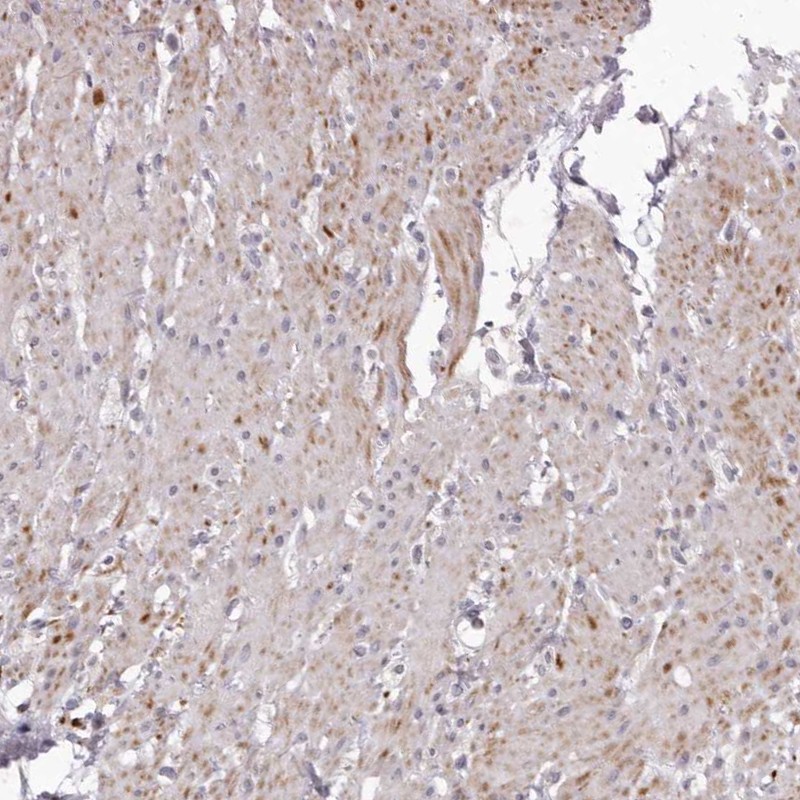

Immunohistochemical staining of human smooth muscle shows cytoplasmic positivity in smooth muscle cells.